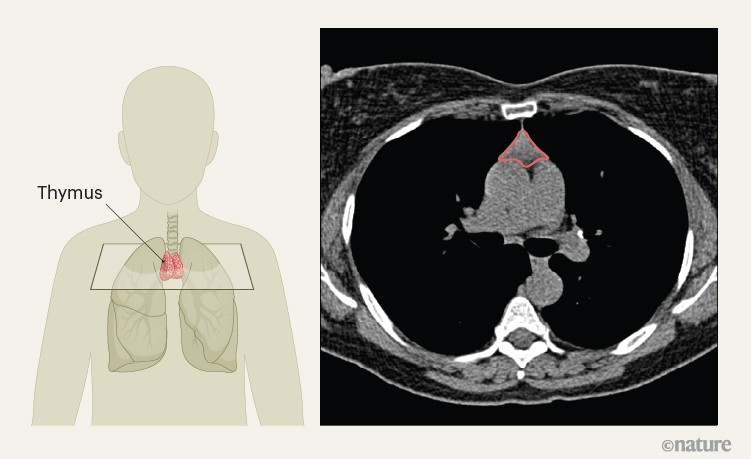

Thymus health is a predictor of lifelong well-being and immunotherapy effectiveness

Nature, Published online: 18 March 2026; doi:10.1038/d41586-026-00633-6It was thought that the thymus serves its purpose for the immune system early in life....

Thymic health and immunotherapy outcomes in patients with cancer - Nature

Nature, Published online: 18 March 2026; doi:10.1038/s41586-026-10243-xA deep-learning approach applied to routine CT scans is used to quantify the health of...

Thymic health consequences in adults - Nature

Nature, Published online: 18 March 2026; doi:10.1038/s41586-026-10242-yAssessing thymic function and health has highlighted the lifelong importance of the th...